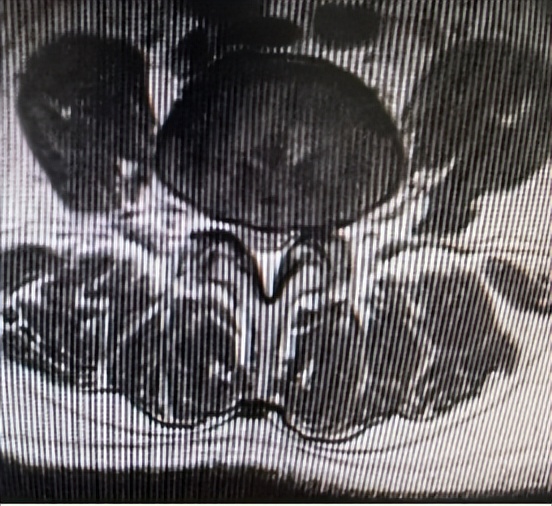

腰3/4、腰4/5两个节段椎管狭窄

66岁男性患者,腰3/4、腰4/5两个节段椎管狭窄,左下肢放射性疼痛、麻木2个月余,间歇性跛行,保守治疗无效。其爱人9年前患腰椎间盘突出症,副主任医师石立刚利用微创椎间孔镜治疗后,至今效果满意。此次慕名前来。